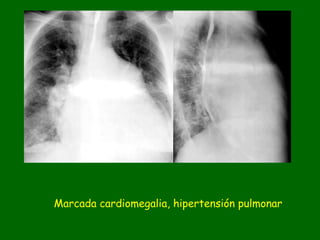

Marcada cardiomegalia, hipertensión pulmonar

Cateter, opacifica Aorta y arteria pulmonar izquierda

Marcada cardiomegalia e incremento del flujo pulmonar